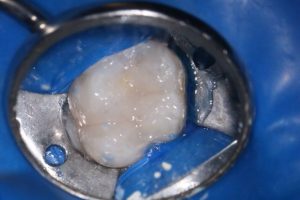

- Ізоляція. Нам необхідно ізолювати причинний зуб від ротової порожнини, щоб попередити забруднення робочого поля бактеріями. Та й не тільки по цій причині. Використовуються системи кофердам або рубердам.

Пацієнт звернувся у клініку з сильним болем після візиту до стоматолога. У зубі виявлена тимчасова пломба. При діагностиці виявлений гострий пульпіт 16 зуба.

За 1 візит було проліковані кореневі канали у 16 зубі. Знайдений 4 канал. Зуб запломбовано методом гарячої вертикальної обтурації. Відновлено фотополімерною реставрацією в цей же візит.